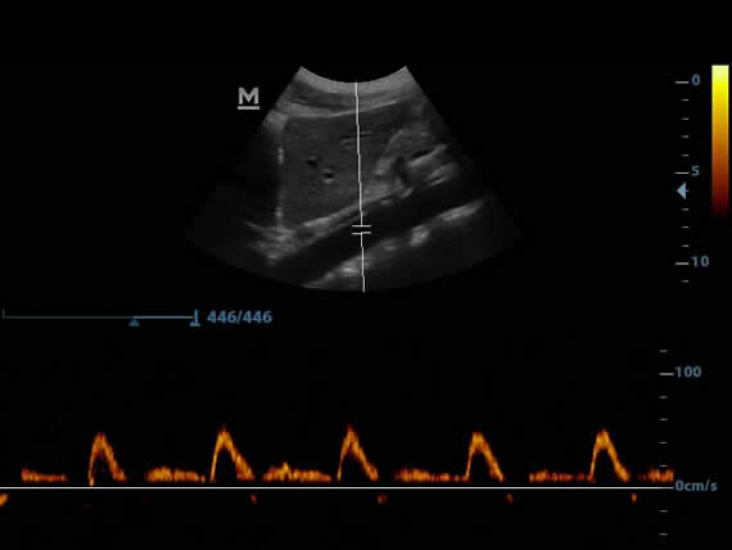

PW

Las funciones de Doppler de onda pulsada (PW Doppler) y trazado automĂĄtico (Auto Trace) revelan detalles del flujo sanguĂneo para un diagnĂłstico mĂĄs completo.